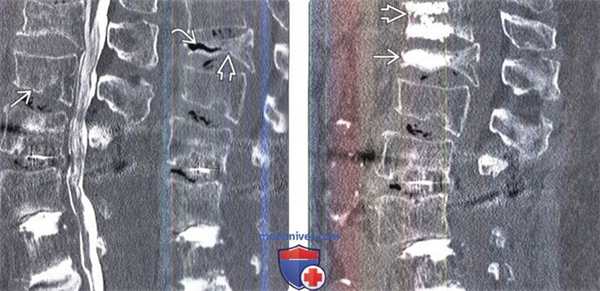

(Слева) КТ-миелография: признаки диффузной остеопении с легкой клиновидной деформацией тела L2 позвонка. В течение ближайшего года у пациента развился остеопоротический компрессионный перелом тела L 1 ЕЯ Существует обратная корреляция между наличием «вакуума» в телах позвонков и минеральной плотностью кости.

(Справа) На сагиттальном КТ-срезе в телах L1 и L2 позвонков определяется гиперденсный метилметакрилат после выполненной пациенту чрескожной вертебропластики этих позвонков.